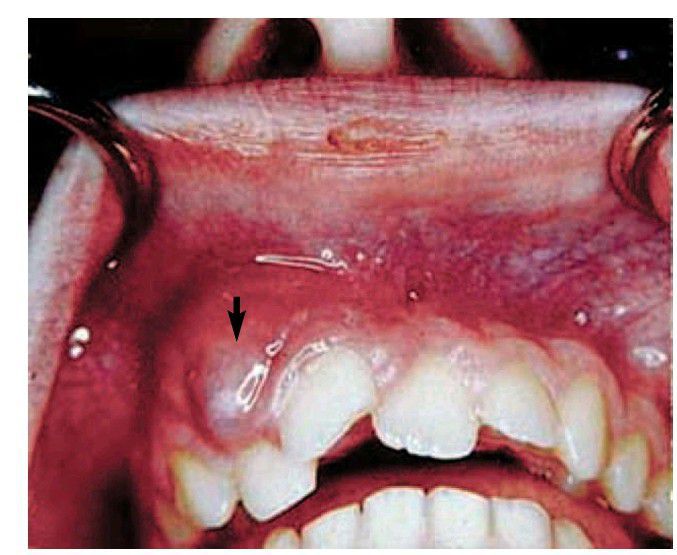

Endodontic infection

Incision and drainage should be performed on this fluctuant swelling (arrow) in conjunction with canal instrumentation.